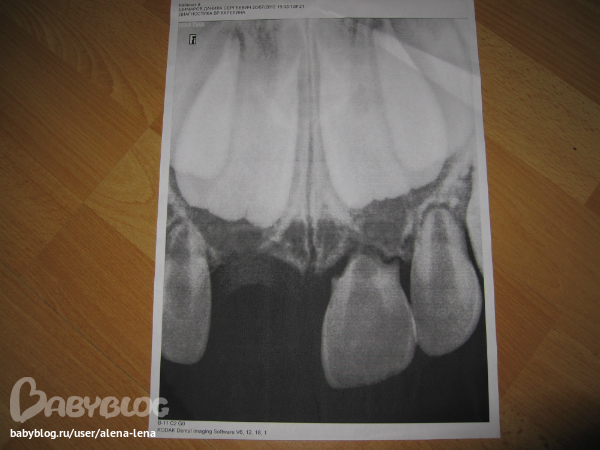

Здравствуйте, летом ребенку было 4г1м его толкнули в саду и пердний 1 резец начал выпадать, пришли в поликлинику, его просто руками легко достали и все, сделали снимок, по нему на тот момент сказали, корли резцов разсосались, зачатки есть, но нет корней и что 2 резец на подходе.

снимок сденал в июле, когда 1 зуб достали,